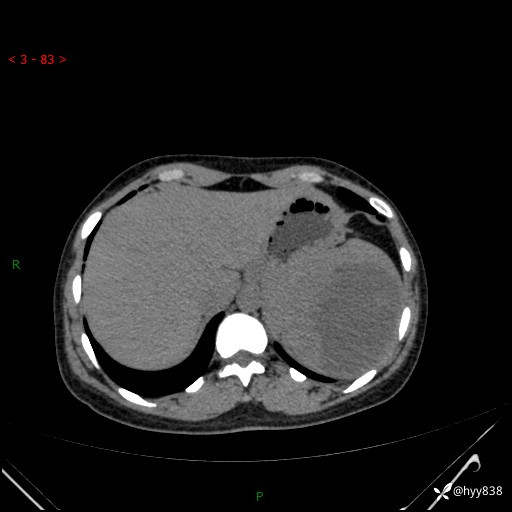

患者性别:男

患者年龄:44岁

主诉:外院超声发现脾脏占位,来我院进一步诊治。

辅助检查:CT

临床诊断:脾脏占位

脾脏CT平扫+增强(动脉期+静脉期)